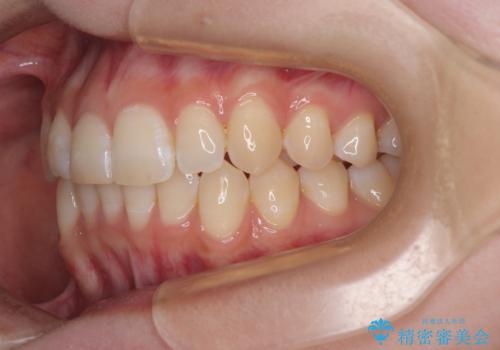

- 上下前歯の重なりを気にして来院された患者様です。

安価なインビザラインパッケージを用いての治療を希望されており、デコボコの程度が中等度であったため、インビザライン・モデレートを用いて矯正治療を行うこととしました。

インビザライン・モデレートは、製作できるアライナーの枚数に制限があるため、移動可能な量に限りがあるものの、インビザライン・ライトよりも枚数が多いため、幅広い症例に対応可能です。